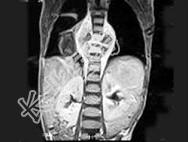

- 单项选择题男,8岁, 咳嗽、咳脓痰,背部肿痛。结合图像, 最可能的诊断是 ( )

E、脊椎结核